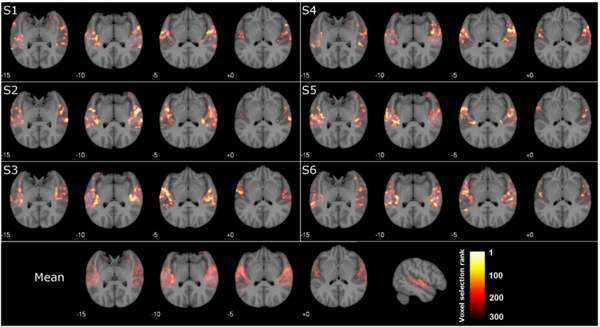

他首先使用 fMRI 和 EEG 的组合来记录 18 名参与者在听 36 种不同音乐时的大脑活动,他确定了几个对音乐有选择性反应的大脑区域:小脑、海马旁回和左侧区域和右颞叶。